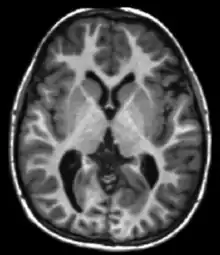

T1 and T2

Each tissue returns to its equilibrium state after excitation by the independent relaxation processes of T1 (spin-lattice; that is, magnetization in the same direction as the static magnetic field) and T2 (spin-spin; transverse to the static magnetic field). To create a T1-weighted image, magnetization is allowed to recover before measuring the MR signal by changing the repetition time (TR). This image weighting is useful for assessing the cerebral cortex, identifying fatty tissue, characterizing focal liver lesions, and in general, obtaining morphological information, as well as for post-contrast imaging. To create a T2-weighted image, magnetization is allowed to decay before measuring the MR signal by changing the echo time (TE). This image weighting is useful for detecting edema and inflammation, revealing white matter lesions, and assessing zonal anatomy in the prostate and uterus.

The standard display of MR images is to represent fluid characteristics in black-and-white images, where different tissues turn out as follows: